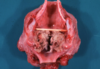

3

Q

This is the stomach of a horse. What lesion is shown here?

A

equine gastric ulceration